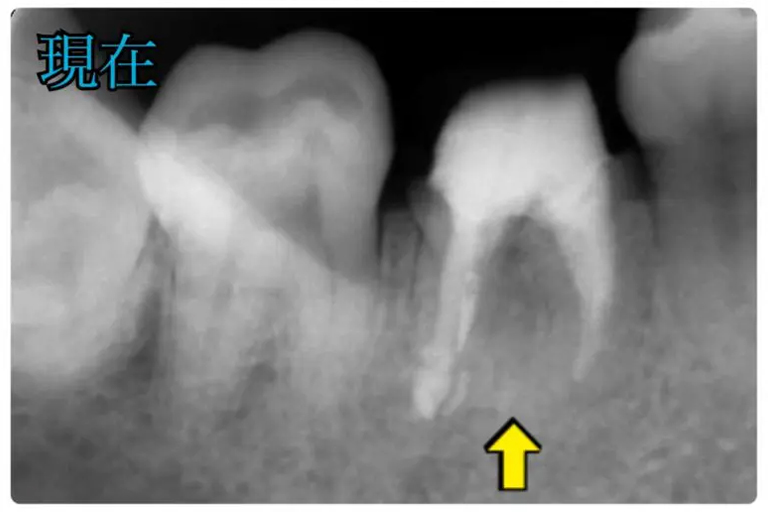

何度根管治療をしても治らないという患者様

術前

術後

| 年代/性別 | 30代/女性 |

|---|---|

| 症状 | 違和感とイヤな臭いがする 抜歯かもと言われた |

| 費用 | 初診診断料:¥16, 500

感染根管治療:¥143, 000 リトリートメント:¥44, 000 パーフォレーションリペア:66, 000 ファイバーコア:¥38, 500 オールセラミックス:¥187, 000 再生外科治療:¥121,000 |

| 備考 | メリット:将来的に歯を保存出来る デメリット:歯科医師に高い技術が求められる |